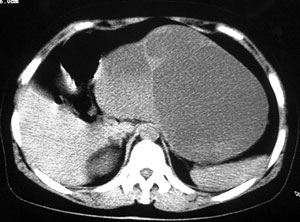

强化片

胰腺体尾部囊实性占位,有分隔.内无脂肪及钙化等组织.胰腺囊腺瘤.;脾大。

胰腺体尾部囊实性占位,有分隔.其内无脂肪及钙化等组织.周围脂肪间隙清,1:胰腺囊腺瘤.

问患者过去有无胰腺炎的病史,2:考虑到假性囊肿。

胰腺体尾部囊实性占位,有分隔.内无脂肪及钙化等组织.胰腺囊腺癌可能性大

诊断很明确:胰腺囊腺癌。

以下是引用守望可可西里在2006-8-30 10:57:00的发言:[br][br] 定位:胰腺体尾部。[br] 定性:胰腺囊腺癌可能性大。[br] 理由:胰腺体尾部呈多囊状分叶,部分病灶与前腹壁粘连,且下部形态不规则,毛糙不整、凸凹不平。囊壁厚薄不一致,多个大小不等壁结节突入,囊壁及壁结节明显不均匀强化。偏右侧囊内见液-液平面样相对高密度,呈与壁结节类似强化。性质:1.出血?2.壁结节?